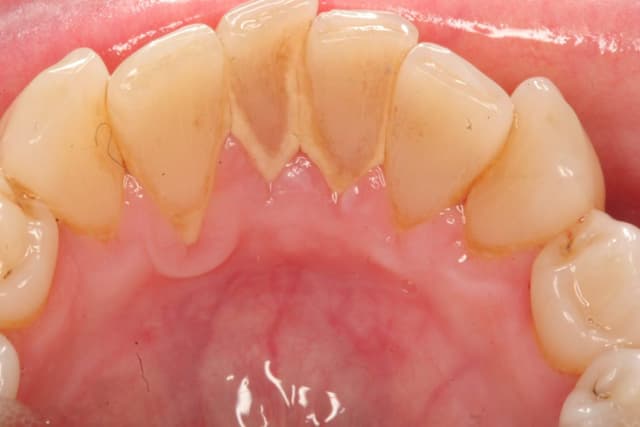

Cao răng là tổ hợp cặn lắng cứng của các muối vô cơ (bao gồm canxi carbonat và phosphate) kết hợp với các cặn lắng mềm (bao gồm mảnh vụn thức ăn, các khoáng chất trong khoang miệng), vi khuẩn, tế bào chết biểu mô, cặn lắng sắt trong huyết thanh. Vị trí bám của […]

Cao răng là tác nhân chính gây ra một số bệnh lý nha khoa nguy hiểm như sâu răng, viêm nha chu, hôi miệng… Bởi vậy, các bác sĩ luôn khuyến cáo mọi người cần thực hiện lấy cao răng thường xuyên tại nha khoa để phòng ngừa bệnh lý. Việc tìm hiểu nguyên nhân […]

Cao răng bám chặt trên răng lâu ngày nếu không được xử lý sẽ dẫn tới những hậu quả vô cùng nguy hiểm đối với sức khỏe răng miệng. Vậy cao răng hình thành như thế nào, làm sao để loại bỏ cao răng? Bài viết sau đây sẽ giải đáp cho bạn những thắc […]